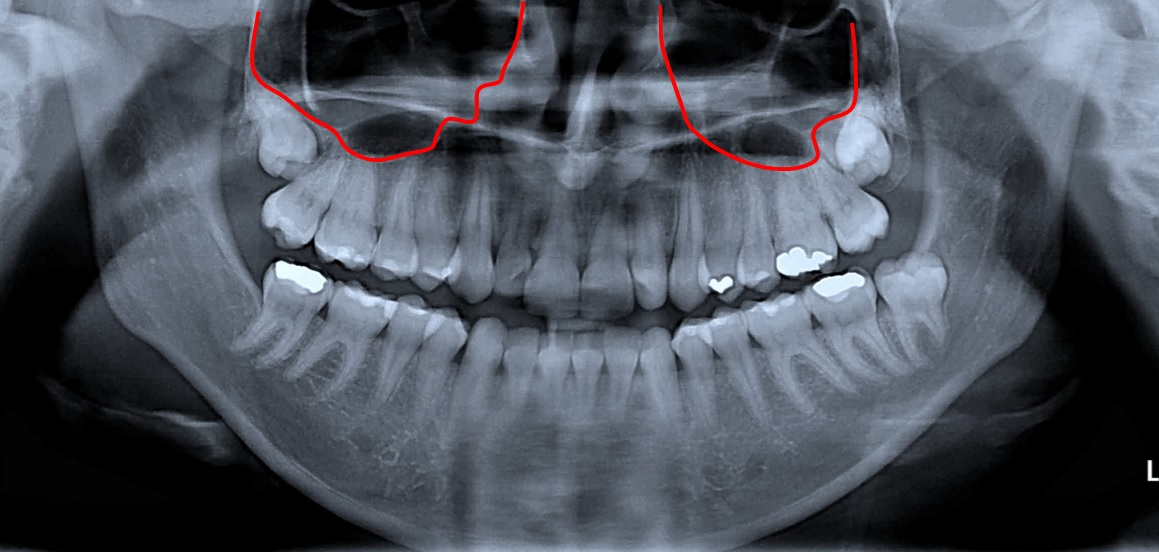

위턱에 있는 사랑니를 뽑을 때도 합병증이 있을 수 있습니다.

바로 상악동 천공입니다.

방사선 사진에서 표시해둔 부분이 상악동이라는 공기 주머니 입니다.

상악동은 코(nasal cavity)와 연결되어있습니다.

두개골의 중량감소, 목소리의 울림부여, 호흡된 흡기의 습도 증가, 흡기 중 발생된 내압의 차이를 감소시키는 등의 기능이 있습니다. 각설하고…

위턱의 사랑니와 상악동 사이의 뼈가 얇은 경우가 대부분이기 때문에, 사랑니를 뽑을 때 상악동의 뼈와 점막이 같이 제거되면서 입안과 상악동이 연결되는 경우가 생깁니다.

이것을 ‘상악동 천공’이라고 합니다.

코와 상악동은 연결되있다 보니, 상악동 천공이 발생하면 입안과 코가 연결된 것과도 같아집니다.

그래서 사랑니를 뽑고 난 후 코피가 나거나, 물을 마실 때 코로 물이 나오기도 합니다.